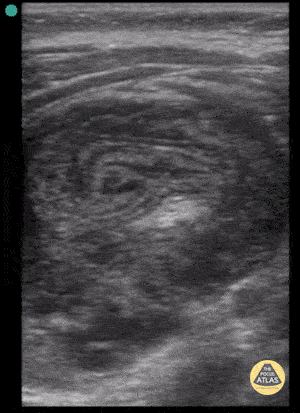

Peds-Gastrointestinal - Pseudokidney Sign - Intussusception

23 month old with ileocolic intussusception. Pseudokidney sign seen here due to oblique orientation of the linear transducer. Contributor: Antonio Riera, MD